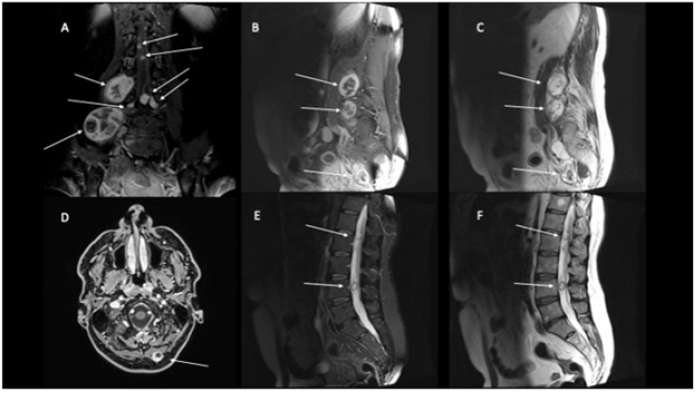

Also, in this district do not signs of muscle irritation was evident. In view of these “leopard spot” findings identifying a multineuropathy rather than a polyneuropathy was then carried a complete blood test of first and second level including blood count, thyroid hormones, TSH, dosage of vitamin B12, erythrocyte sedimentation rate, C-reactive protein, ANA, ENA, glycated hemoglobin, fasting blood glucose, liver and kidney function indices and antibody assay against onconeural antigens which were all negative. A lumbar puncture was also carried out, negative. For the involvement of the right biceps femoral muscle, in addition to an MRI of the brain and lumbosacral marrow, a bilateral magnetic resonance imaging of the thigh was also performed, with evidence of multiple schwannomas, of which the largest one present along the right L5 root territory in the context of m. psoas (figure one, panel A). These findings did not affect the vestibular nerves (figure one, panel D).

Figure 1: Brain, Rachis and Thigh MRI show multiple parenchymatous formations with a heterogeneous structure in the context of the muscle belly of the psoas, extending up to the ileus muscle and to the right lateral side of the L4 and L5 vertebrae. Findings with the same characteristics in correspondence were found at paraspinous nerve roots from L3 to L5, cauda and at the right paramedian occipital region (white arrow). T1 hyperintense components indicating hemorrhage or fatty degeneration occurs in a small fraction. Same lesions show T2 hyperintense, because cystic degeneration is common, and T1 with gadolinium showing marked and non-homogeneous contrast enhancement. Unlike neurofibromas, which tend to grow centrally from a nerve, schwannomas more frequently tend to have eccentric growth [1].